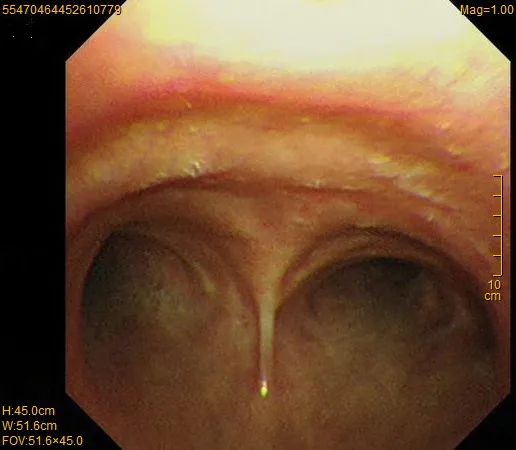

气管镜图:气管隆突